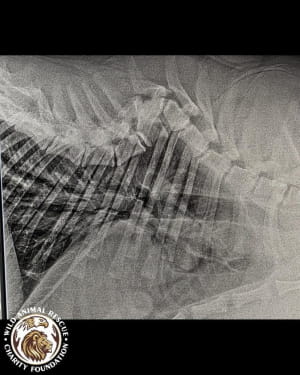

Тварині лише рік, але вона вже стала глибоким інвалідом. Тигриця не здатна самостійно підвестися і ледве пересувається, спираючись виключно на передні лапи. Після ретельного обстеження ветеринари були шоковані станом кісток молодого хижака.

• Дегенеративні зміни у хребетному стовпі.

• Загальна деформація кісток скелета.

Лікарі утримуються від оптимістичних прогнозів. Процес лікування ускладнюється великою масою тіла хижака та сильною крихкістю кісток, які просто не витримують навантаження. Оскільки тигриця фізично не може довго лежати нерухомо, терапія стає справжнім викликом.